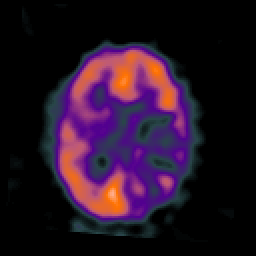

SPECT TC Study #3 -- Slice #33

[Home][Help][Clinical][Tour 1][Tour 2][Tour 3] Slice 33